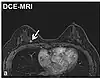

| Dynamic contrast enhanced | DCE | Measures changes over time in the shortening of the spin–lattice relaxation (T1) induced by a gadolinium contrast bolus.[36] | Faster Gd contrast uptake along with other features is suggestive of malignancy (pictured).[37] | ![]() | |